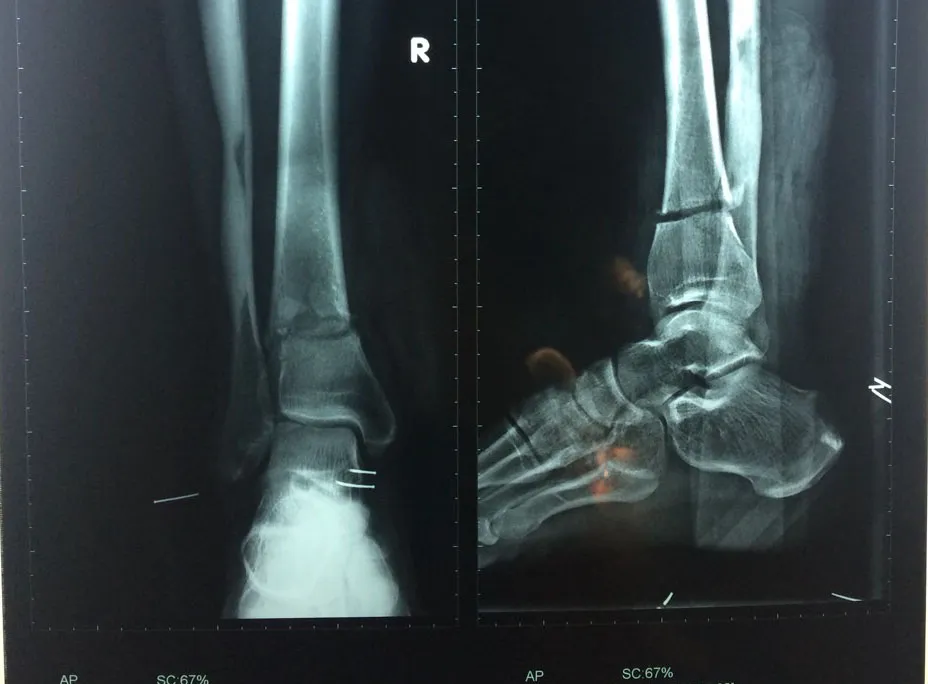

Kết quả chụp X-quang cho thấy chân phải ông C. gần đứt lìa. Ảnh: HÒA KHÁNH